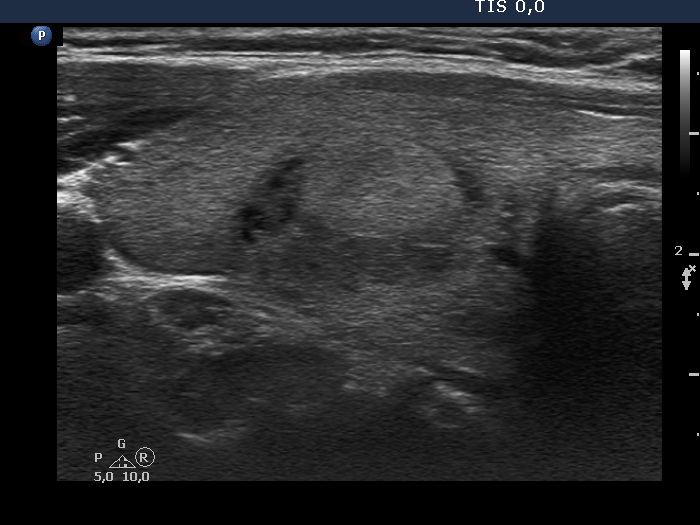

Right lobe, longitudinal scan

Right lobe, longitudinal scan. In this section, the echonormal and hypoechoic areas are roughly equal.